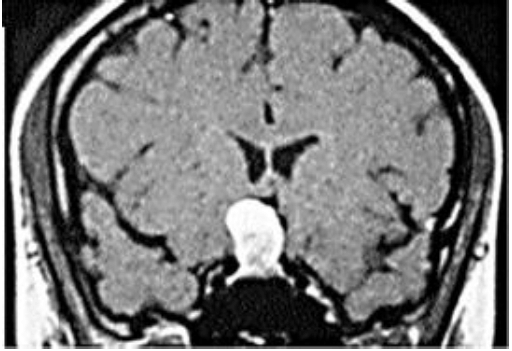

Observe a ressonância magnética, abaixo:

A imagem acima indica Cisto da bolsa de Rathke - RM com uso de gadolíneo, corte coronal. Observa-se massa hiperintensa, em T1 de crescimento: